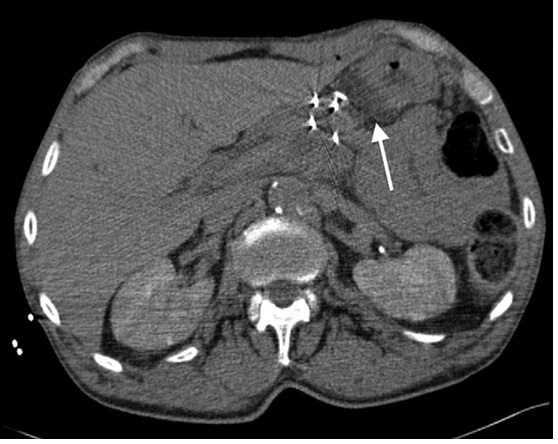

經(jīng)皮消融計(jì)劃和實(shí)行兩次消融會(huì)話來避免一次使用多于六根探針。病人全身麻醉后,4個(gè)15cm的單極探針,納米刀Nanoknife; AngioDynamics, Latham, New York 在方形配置平均1.8cm間距的超聲波指引下放置在腫瘤的中央和側(cè)面。帶有造影劑的CT影像用來評(píng)估相應(yīng)血管的探針位置和探針距離。(圖2)。所有探針有1cm的電極接觸其中一個(gè)探針用的是經(jīng)肝途徑。一個(gè)22Ga脊椎穿刺針(Becton Dickinson, Franklin Lakes, New Jersey) 在US指引下放置在胃肝處來分離無菌水。

圖2:IRE針放置的位置